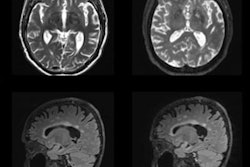

The needle is a critical component of the Arrow EZ-IO intraosseous vascular system, which can be used when intravenous access is difficult or impossible to obtain in emergent, urgent, or medically necessary cases, according to the vendor. With the new MR-conditional labeling, clinicians can now continuously care for patients who require MRI scans without interruption to the established site for vascular access, Teleflex said.